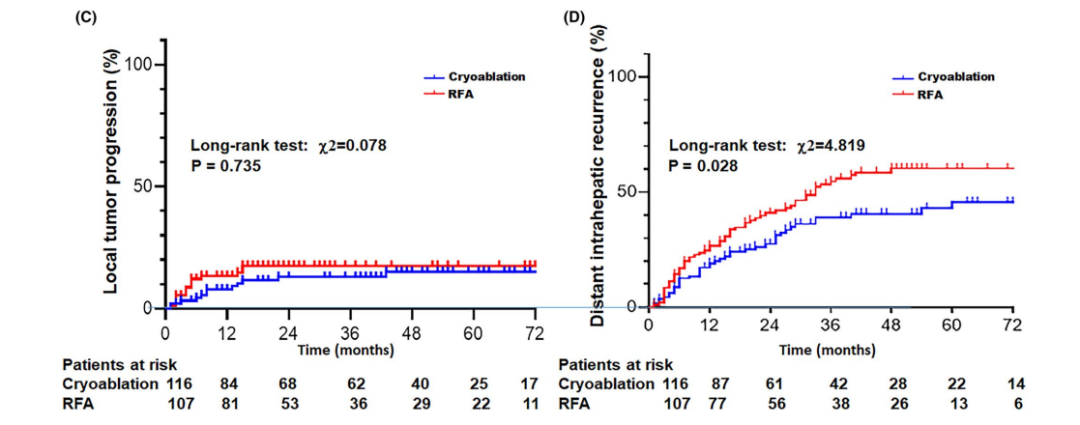

③ 局部肿瘤进展率曲线和直径>3 cm病灶局部肿瘤进展率曲线